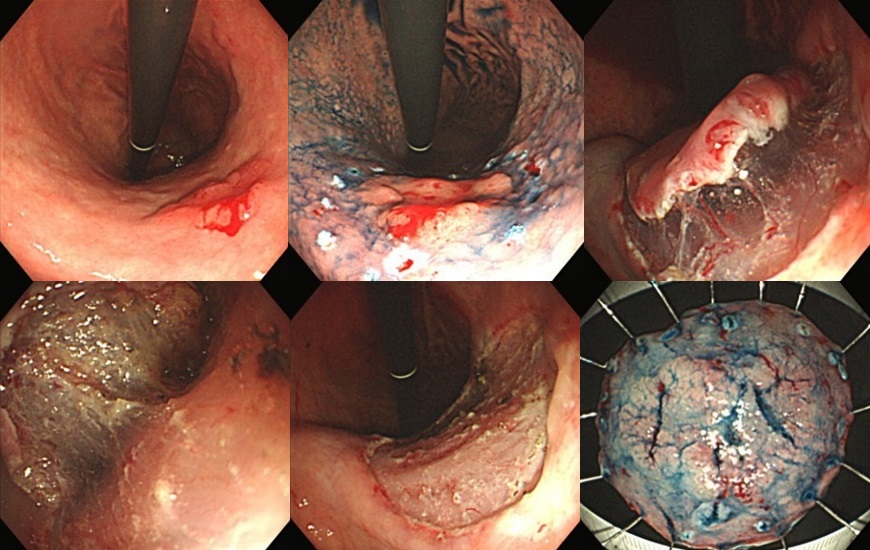

『早期胃癌に対する内視鏡的粘膜下層剥離術(ESD)』